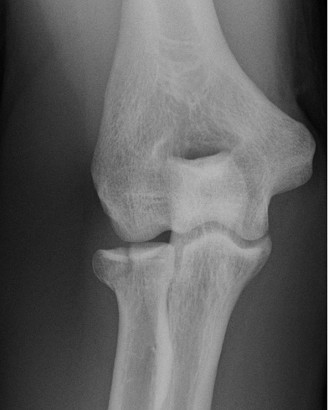

The patient undergoes resection arthroplasty with antibiotic cement spacer and a 6-week course of IV antibiotics. He returns to clinic 4 months later with improved pain, CRP <3, however, on examination he has a positive belly press sign and increased external rotation compared with the contralateral shoulder. Imaging is shown in Figure 2–57.

Figure 2–57

What will likely be the definitive management of his infection?

- Maintenance of antibiotic cement spacer

- Explanation of antibiotic cement spacer with total shoulder arthroplasty

- Additional 6 weeks of antibiotic therapy followed by rechecking CRP

- Explanation of antibiotic cement spacer with reverse total shoulder arthroplasty

The correct answer is (D). The patient has completed his course of antibiotics and his spacer and is now an appropriate candidate for explanation of the cement spacer with revision shoulder arthroplasty, therefore Choices A and C are incorrect. The patient’s clinical examination findings point to rotator cuff tear (specifically subscapularis) which has occurred in the interval between his obtaining his initial total shoulder arthroplasty and his current examination. Therefore, total shoulder arthroplasty (Choice B) is contraindicated, and the patient should have a reverse total shoulder arthroplasty. Objectives: Did you learn...? Recognize the clinical presentation of a patient with infection after total shoulder arthroplasty?